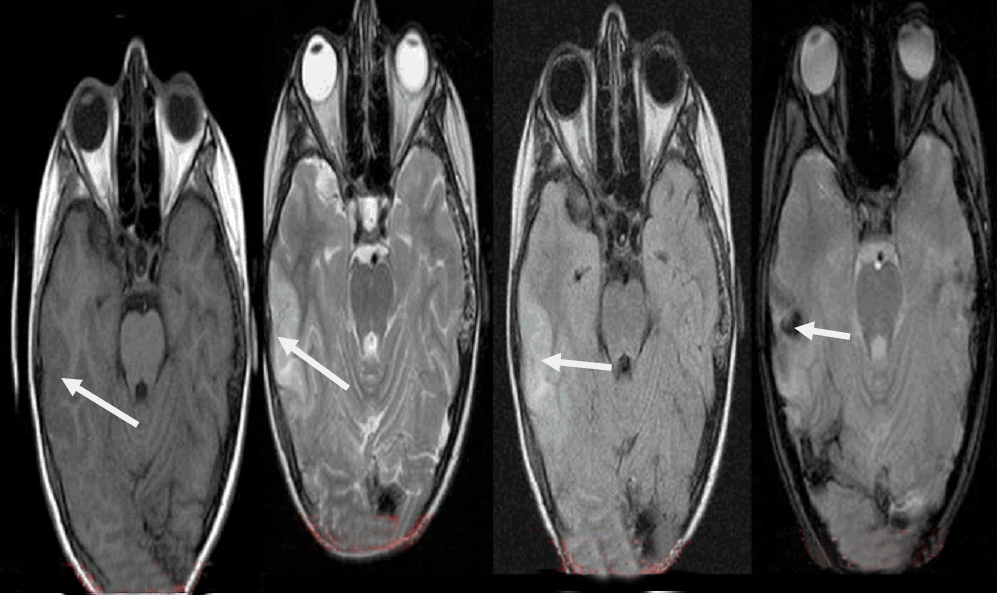

Patient was admitted in the neurosurgical clinic and was initiated on anticonvulsant medication. Neurological and ophthalmological examination did not reveal any focal deficits. Magnetic resonance imaging performed the same day revealed edematous configuration of the nearby gyri with concurrent presentation of hemorrhagic elements (Figure 2).

Figure 2: Initial magnetic resonance imaging scan, within the first day after the event. Arrows depict the pathologic changes at T1W, T2W, FLAIR and T2 GRE sequences (images corresponding from left to right).